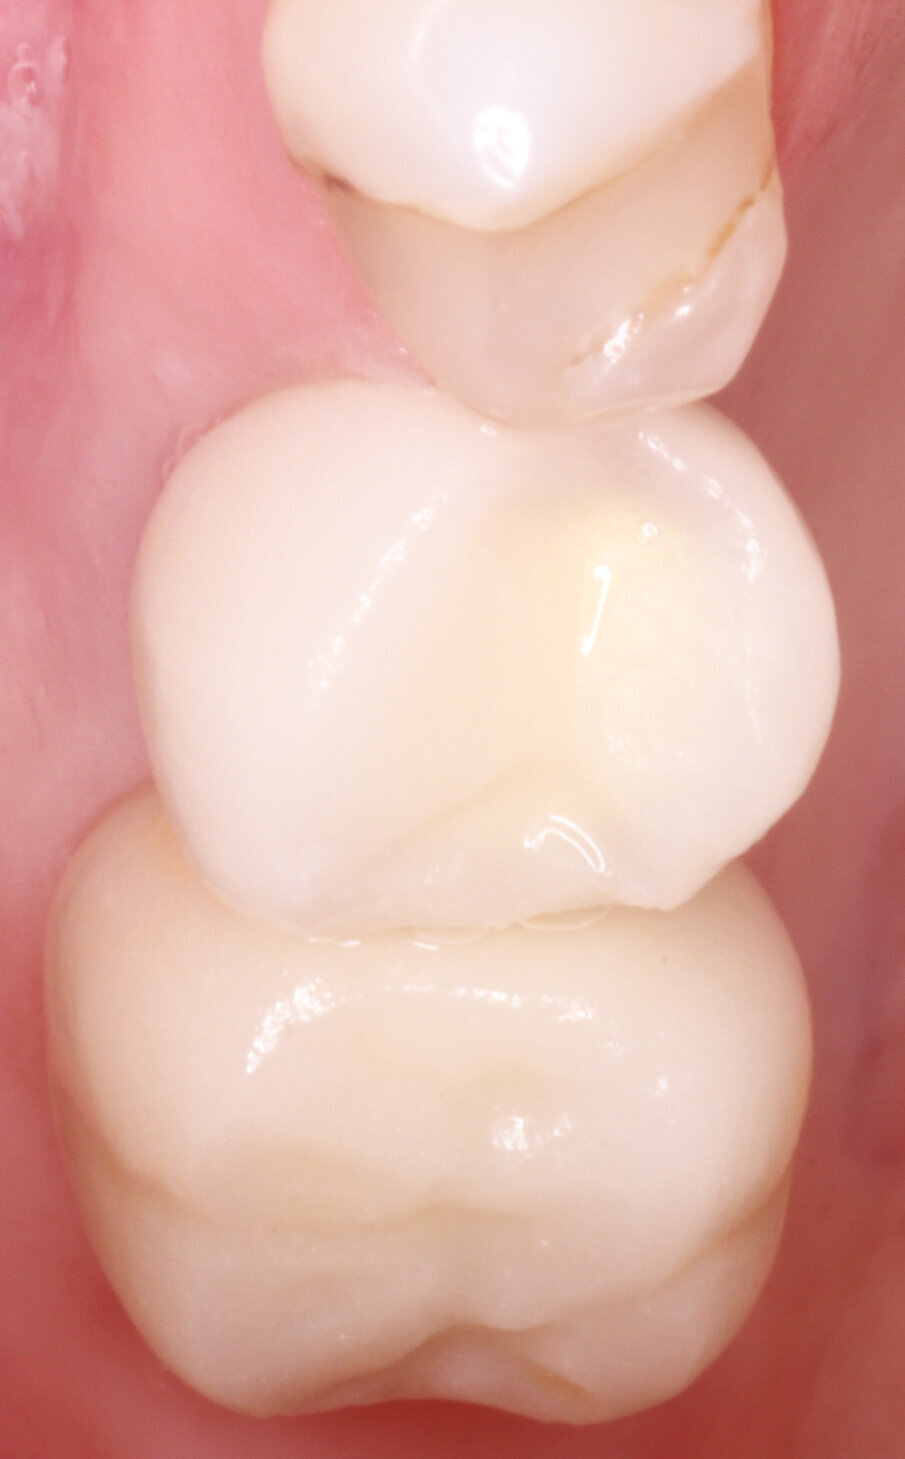

Figs.16: Final zirconia crowns placed

Figs.17: Final zirconia crowns placed